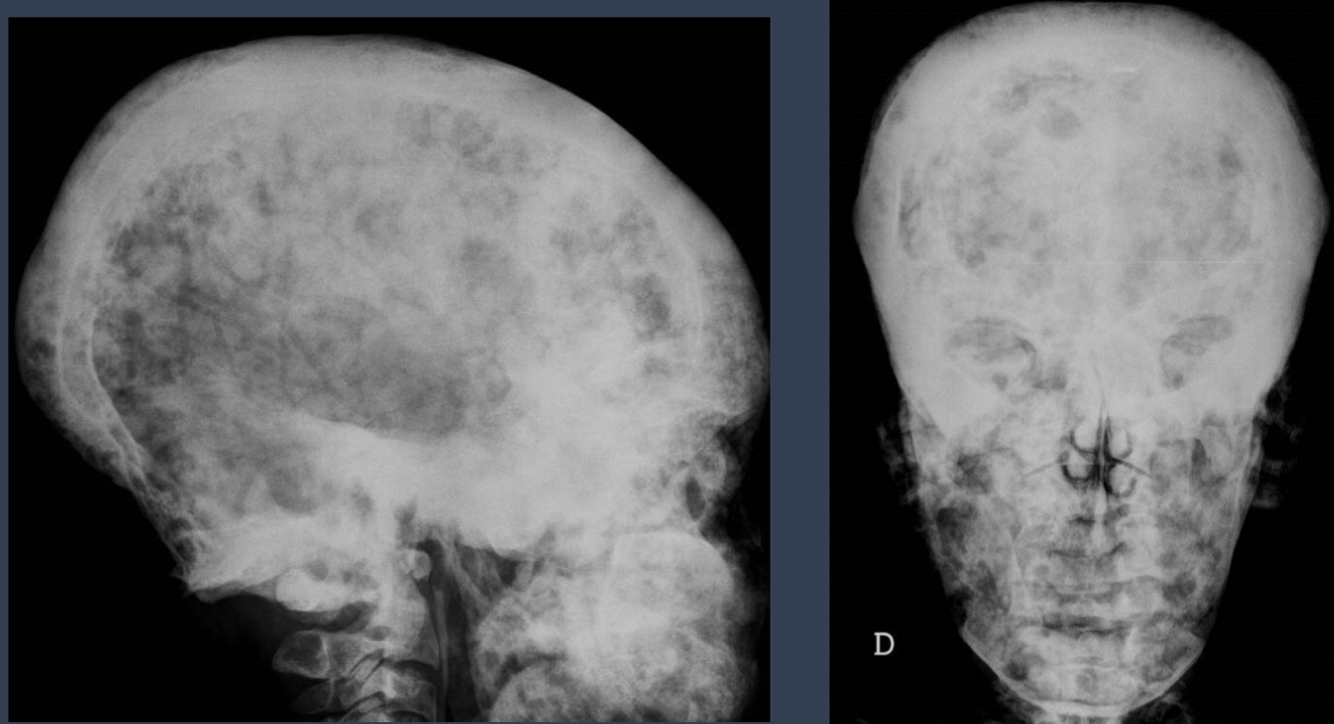

what is this?

multiple myeloma

how do you describe it?

paget disease

cotton wool appearance basilar impression (tip of the odontoid process projects above the foramen magnum)